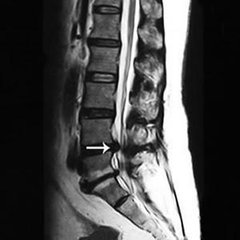

导读: 椎管狭窄在老年人当中比较常见的骨科疾病,椎管狭窄引起的跛行是指病人直立或行走时,下肢有逐渐加重的沉重感、疼痛、麻木、乏力等不同的感觉,以至于不得不改变姿势或停止行走。

导读: 很多中老年人会患有腰椎管狭窄症,腰椎管狭窄会压迫神经,导致一系列症状。腰椎管狭窄症多见于中老年人,是腰腿疼和下肢行走无力的常见原因。腰椎管狭窄患者行走过程中,会出现腰腿疼痛和下肢酸困、麻木、无力、跛行

导读: 得了腰椎管狭窄不仅会给患者带来身心健康的伤害,还会给生活工作带来不少的麻烦。据专家讲解到因某些因素发生骨性和纤维结构的异常,导致一处或多处管腔狭窄,压迫硬脊膜与神经根出现临床症状。

导读: 腰椎管狭窄是指各种形式的椎管、神经管以及椎间孔的狭窄,以及软组织引起的椎管容积改变及硬膜囊本身的狭窄等引起的一系列腰腿痛及一系列神经系统症状出现。